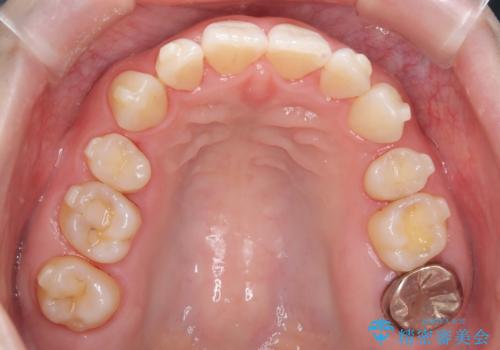

- 治療計画

- 患者様は、上下顎の歯列不正と前歯部の突出感を主訴としてご来院されました。診断の結果、上顎左右第一小臼歯を抜歯することでスペースを確保し、歯列全体を整える方針としました。本来はワイヤー矯正が推奨されるケースですが、患者様のご希望により、透明なマウスピース型矯正装置「インビザライン」を使用した治療計画を立案しました。治療期間は約3年で、奥歯の噛み合わせを維持しながら、徐々に前歯の位置を整えました。